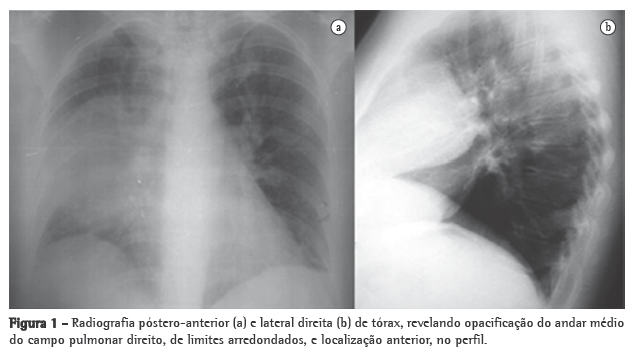

INFILTRAZIONE LEUCEMICA LINFADENOPATIA Leucemia acuta, sottotipo a cellule T radiografie del torace di un bambino di 4 anni che mostrano (a) slargamento mediastinico causato da ingrossamento timico;. A piccole cellule massa centrale con adenopatia ilare;. • segni legati alla presenza di ematoma mediastinico slargamento del profilo del mediastino.

INFILTRAZIONE LEUCEMICA LINFADENOPATIA Leucemia acuta, sottotipo a cellule T radiografie del torace di un bambino di 4 anni che mostrano (a) slargamento mediastinico causato da ingrossamento timico;. Il mediastino è un compartimento anatomico a forma di clessidra che occupa lo spazio centrale del torace compreso tra i polmoni, in cui sono contenuti il cuore, i grandi vasi ed altre strutture Tutti gli organi e strutture in esso contenuti (cuore, esofago, trachea, grossi vasi e numerosi linfonodi) possono dare luogo a patologie che prendono il nome di "mediastiniche". Mediastino translation in ItalianEnglish dictionary Showing page 1 Found 97 sentences matching phrase "mediastino"Found in 6 ms.